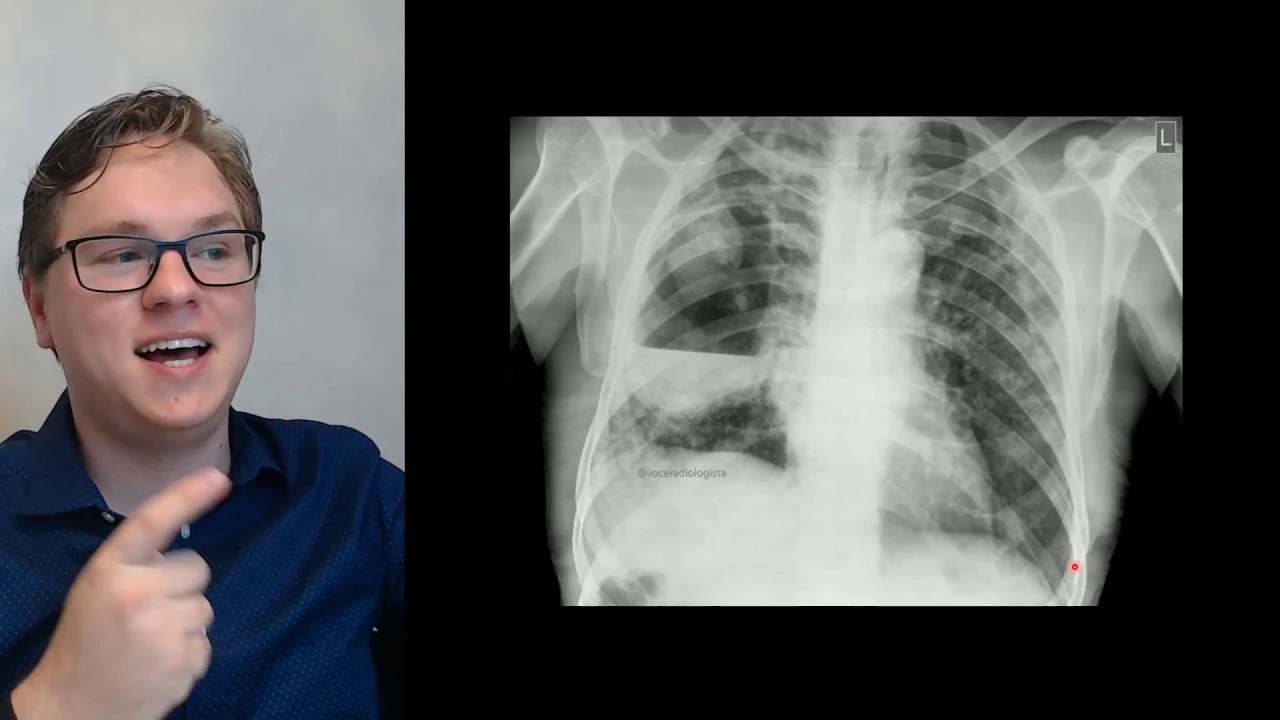

um colega meu nome é joão sou médico radiologista estou aqui para te ajudar a interpretar essa radiografia aqui bom a verdade aqui uma radiografia como essa assim como qualquer radiografia deve ser interpretada num contexto clínico é por isso que é sempre importante a gente saber o motivo da solicitação dos exames e um paciente com febre tosse e dispneia a gente já vai pensar de primeiro hipóteses e que ele esteja com a infecção do trato respiratório nesse caso trato respiratório inferior que que a gente tá vendo né se raio-x a gente vê algumas opacidades algodonosos as

consumir nativas que são áreas de redução da transparência pulmonar às vezes essas roupas cidades são melhor vistas e às vezes elas são mais mal caracterizados como se fossem pontinhas e linhas irregulares esse aspecto de pontos e linhas irregulares você o infiltrado reticulonodular não quer dizer que é vírus não quer dizer que é pneumonia só uma forma de descrever o que você tá vendo é o pulmão mais sujinho e esse aspecto mais algodonoso você pode falar opacidades algodonosos ou consolidar ativas tá é um padrão broncopneumonico digamos assim tem todo pulmão esquerdo tem aqui no pulmão direito

também mas o que mais chama a atenção nesta radiografia e eu quero que você se atende se você não tinha reparado a isso ainda é essa área aqui essa área interessante porque o pulmão tá todo meio sujo e essa região parece menos suja do que o resto do pulmão agora quando a gente chega na parte mais inferior ela tem uma área mais consolidada mais densa mais homogênea e essa área de redução homogênea da transparência faz um nível há entre a consolidação a partir da redução da transparência melhor dizendo e o ar então chama isso de

nível hidroaéreo porque daqui para baixo se tá para uma nível é líquido e daqui para cima é ar toda vez que a gente vê um nível hidroaéreo não achei tórax a principal coisa que vai alertar na nossa cabeça tem que ser abscesso pulmonar e aí a gente procura as limitantes a periferia desse nível para identificar as paredes do abscesso então se eu segui aqui esse nível eu chego aqui na periferia dele e vejo que eu posso continuar mais ou menos esse abscesso as paredes desse abscesso meio desse continuam num formato arredondado ou ovalado ar e

isso aí é típico para abscesso pulmonar então achado mais relevante dessa radiografia é uma o pulmonar na projeção do terço médio do pulmão direito por que que eu digo projeção porque eu tô numa radiografia em frontal ou seja ela não eu não tenho aqui o perfil para ver exatamente onde é só juntar projetada sendo logo inferior no lobo superior ou no lobo médio o ideal é teu perfil para localizar exatamente a lesão se eu não tenho eu posso dizer que tá na projeção e aqui marcado para você comparar aqui a radiografia com infiltrado reticulonodular e

eu para cidades alveolares algodonosos em ambos os pulmões nos terços médio superior e inferior dos dois lados e aqui é direita eu tenho um volumoso abscesso pulmonar mas vai com calma não dá para chamar direto de abscesso pulmonar se eu não tiver clínica do paciente na mão é com a clínica de febre tosse dispneia aguda que eu posso chamar esse nível hidroaéreo no pulmão de um abcesso pulmonar certo mas o que que é mesmo abscesso pulmonar agora que você já sabe o achado no raio x você precisa saber do que quem está falando abscesso pulmonar